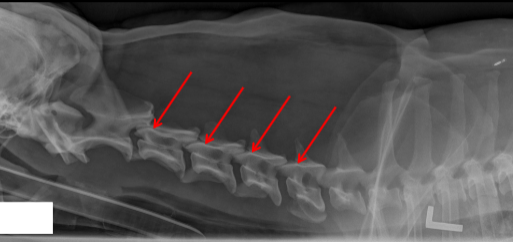

ID

Caudal Articular Process

Cranial Articular Process

Transverse Foramina

Alar Notch

Lateral Vertebral Foramen

Cranial Costal Fovea

Accessory Process